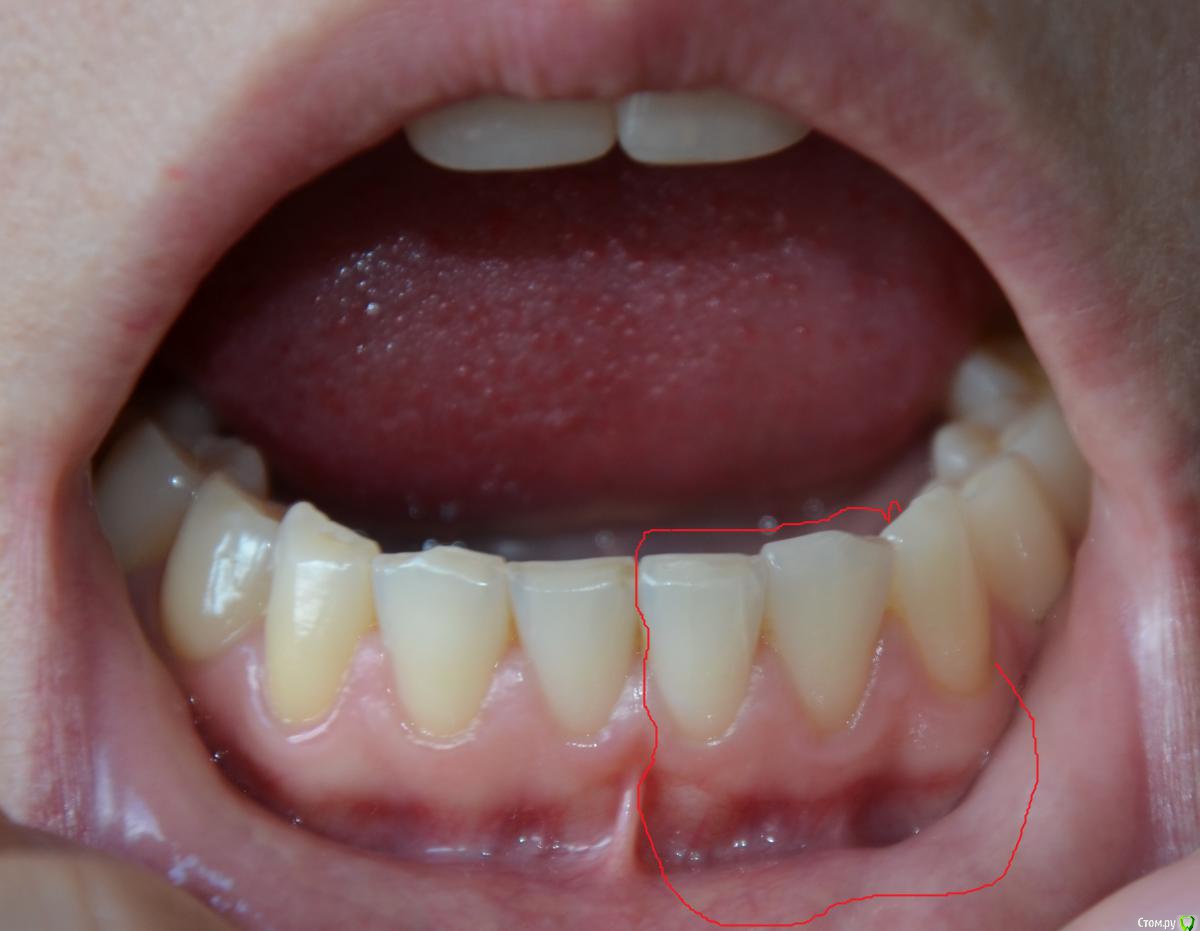

Olga82 Опубликовано 24 апреля, 2015 Поделиться Опубликовано 24 апреля, 2015 Прошу совета в нижеследующих проблемах:Зубы начала лечить с января 2105 года(Рентген-снимок именно до лечения прилагается), вылечила уже все зубы кроме одного(26-й или 16-й, не знаю, с какой стороны правильно вести отсчет).Проблема №1:Сделали верхние передние(замена пломбы+выравнивание режующей поверхности посредством пломб на обоих зубах+полировка(шлифовка).После шлифовки появились сначала белый точки, потом на зубе 1(фото прилагается) при чистке зубов прямо отошел тонкий кусочек как пленка полупрозначная зуба(зуб вообще был здоровый, только неровный рез), теперь там выемка как бы вглубь), на зубе 2 сейчас неровная как неотшлифованная поверхность (на фото, к сожалению, плохо видно, невозможно снять), на зубе 3 идет полоса на эмали-опять-таки как дефект шлифовки.Как это понимать? Топорная шлифовка или мои проблемы с зубами? дело в том, что я кормлю грудью уже 2 года, мой стоматолог сказал, что в зубах судя по всему мало кальция, поскольку после несильной заморозки один из них быстро побелел.Что мне предпринять? Дошлифовать недошлифованное?Или не трогать, а провести реминерализацию/глубокое фторирование/пропить курс витаминов и только потом их трогать? Какова судьба моих любимых передних зубов-печальная или смотреть оптимистично? Проблема №2:Дней пять как стали ныть нижние зубы(по фото обвела), их не лечили, они вроде как здоровые, небольшой коричневый налет присутствует с внутреннего края на одном, стоматолог его немного поскреб ....и смолчал...ничего не сказал...это камень, я правильно понимаю?Боль постоянная, тупообразная.Я полна мыслей об отстутствии кальция в моих зубах и слабости эмали купила пасту Лакалют сенситив, чищу ей второй день-пока нет результата, как болело, так и болит, полощу ротовую полость содой.Что это может быть?К стоматологу записана на 3 мая, не знаю, доживу ли до этого срока.Надо срочно бежать ?Спасибо всем за уделенное время моим проблемам. Ссылка на комментарий

Olga82 Опубликовано 25 апреля, 2015 Автор Поделиться Опубликовано 25 апреля, 2015 Вас сюда на задание Шон Коннер отправил? Да все что не дополировано, дополировать А у меня зубы не начнут сыпаться-откалываться? Меня пугает, что на каждом полированном белые точки появились(возможно это воздух?), и что произошел скол эмали с №1.До полировок с зубами подобного не происходило.так можно дополироваться до постановки виниров(Нет? В чем может быть причина ноющей боли в нижних передних? Как мне можно её снять до визита к врачу?(несколько дней).Это болезнь десен или чувствительность зубов по большей вероятности? Ссылка на комментарий

faity Опубликовано 25 апреля, 2015 Поделиться Опубликовано 25 апреля, 2015 я написал офигительно длинный пост и случайно все удалил(((поэтому вкратце: отчего могут быть сколы эмали на зубах после полировки и белые точки? сколы из-за неправильного распределения нагрузки во время жевания, неправильное распределения нагрузки- из-за неправильного прикуса, пятна либо недополировали, либо после полировки покрыли адгезивом, чтобы "блястело сразу в кресле" Это чёй-то? У меня показания к удалению только одного зуба(я с номерами уже запуталась, он наверху). показания ортодонтические .Мой врач сказал, что прикус нормальный, без претензий на идеальность, но жить можно без ущерба здоровью зубов.Вы считаете, что в этом есть обязательная необходимость? Прикус патологический и если эстетика вас не напрягает, то артрит височно-нижнечелюстного сустава начнет рано или поздно давать о себе знать. Плюс читайте выше про ударные нагрузки и к чему это приводит. Ссылка на комментарий